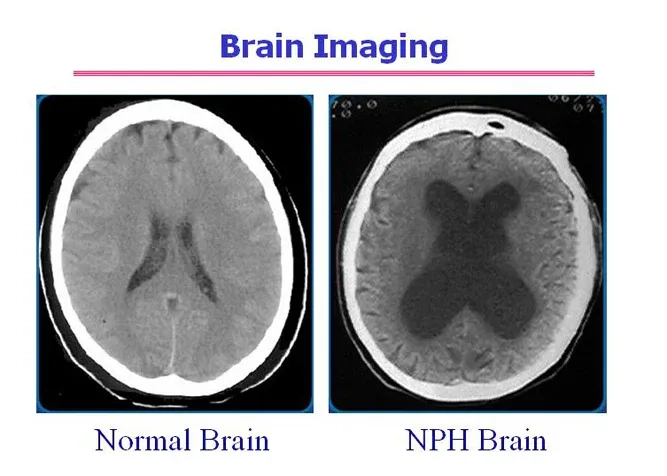

The top Normal Pressure Hydrocephalus images everyone is searching for

MRI brain scan showing enlarged ventricles in NPH